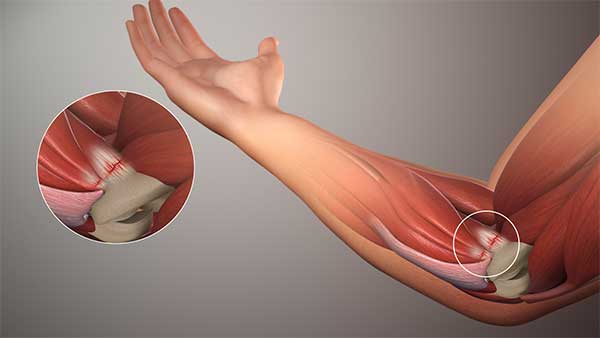

Es la afección más frecuente del codo, existe inflamación de los tendones de los músculos extensores de la mano que se insertan en el epicóndilo. generalmente microdesgarros y cambios en el colágeno produces micro-rupturas que generan inflamación y dolor. Una mala cicatrización ocasiona que el dolor y las molestias se hagan crónicas. Alta incidencia en deportistas y trabajadores con esfuerzos repetidos o sostenidos de las manos.